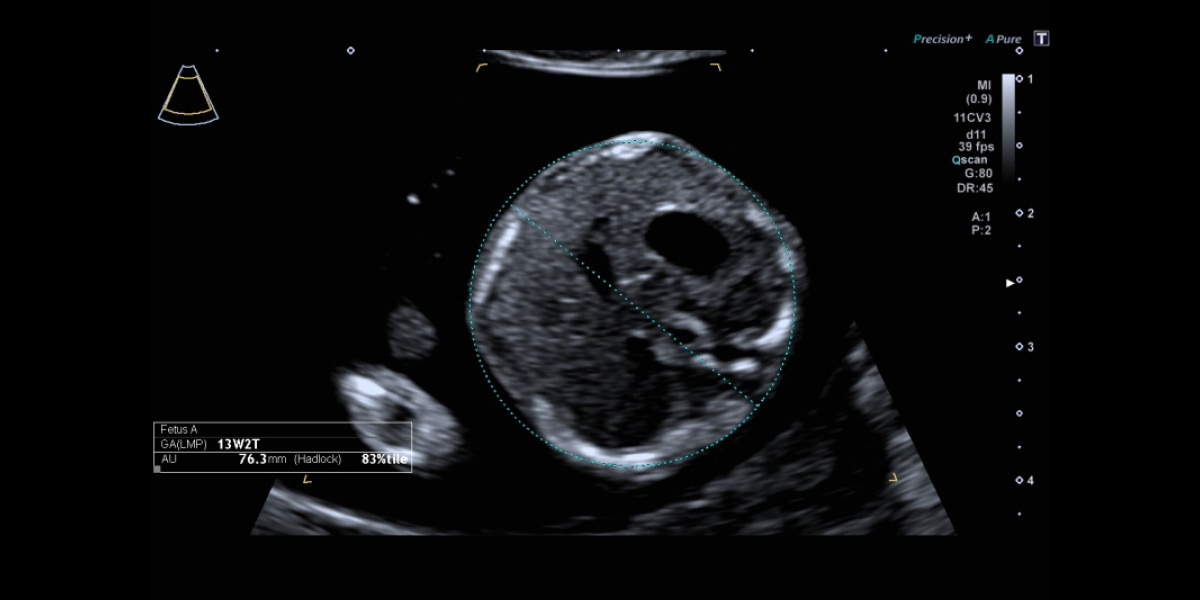

Bildergalerie 1. Schwangerschaftsdrittel (ETS)

Das Baby in der Übersicht. So können Wachstum und Proportionen, Herzschlag und Gesicht gesehen werden.

Bei der Nackentransparenzmessung sind auch Nasenbein und Hirnstrukturen sichtbar und geben unter anderem Aufschluss über die Wahrscheinlichkeit für Trisomie 21.

Kopfform und Großhirnhälften sind unauffällig entwickelt.